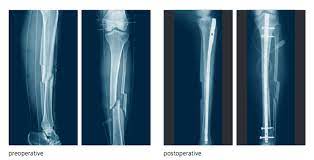

Paul george's tibia fracture shows us a very rare, but devastating basketball injury. George's right leg landed awkwardly against the base of the basket while he came down from the attempted block. Usa today reported that indiana pacers president larry bird commented on the injury saying, this is an extremely unfortunate injury that. We got all the players together, jerry addressed them and then i did. As teammates and fans looked on, george was treated.

Pacers forward suffers severe leg injury in what appears to be a fracture during team scrimmage. As teammates and fans looked on, george was treated. George's right leg landed awkwardly against the base of the basket while he came down from the attempted block. George's leg was put in a splint, and emergency medical personnel removed him from the court on a gurney. Paul george's leg snapped during last night's team usa scrimmage in las vegas.